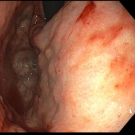

David Farrow, MD; Ajit Ramadugu, MD; Jordan Burlen, MD, BS; Mona Hassan, MD

A 60-year-old woman presented to an outside hospital with hematochezia, hypotension, 4 days of abdominal pain, and shortness of breath.